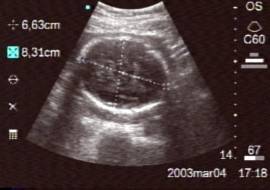

Data inserimento: 28/12/2004

Data esame: 23/12/2004

Strumento: Sonosite

Età paziente: M 64 anni

Neoformazioni surrenaliche bilaterali di maggiori dimensioni al surrene sinistro, asintomatiche.

Elaborazione digitale: Andrea Dini

In collaborazione: Dr. Davide Agostini, Dr.ssa Ornella Orsini